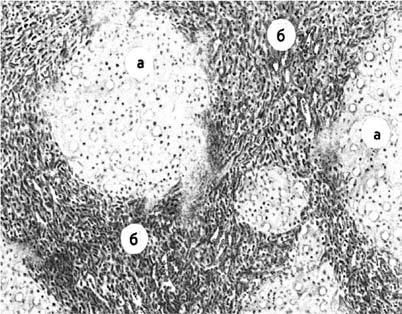

При микроскопическом исследовании дольчатое строение паренхимы печени с характерным расположением венозных сосудов, артериол и желчных капилляров, искажено. Вместо печеночных долек определяются узлы-регенераты, состоящие из округлых, беспорядочно лежащих клеток разного размера. Портальные синусы и центральная вена отсутствуют или резко деформированы. Узлы окружены широкими прослойками соединительной ткани с редкими венозными, артериальными сосудами и желчными потоками (рис. 78).

Рис. 78. Микроскопическая картина цирроза печени:

А – узлы-регенераты; Б – широкие соединительнотканные перемычки